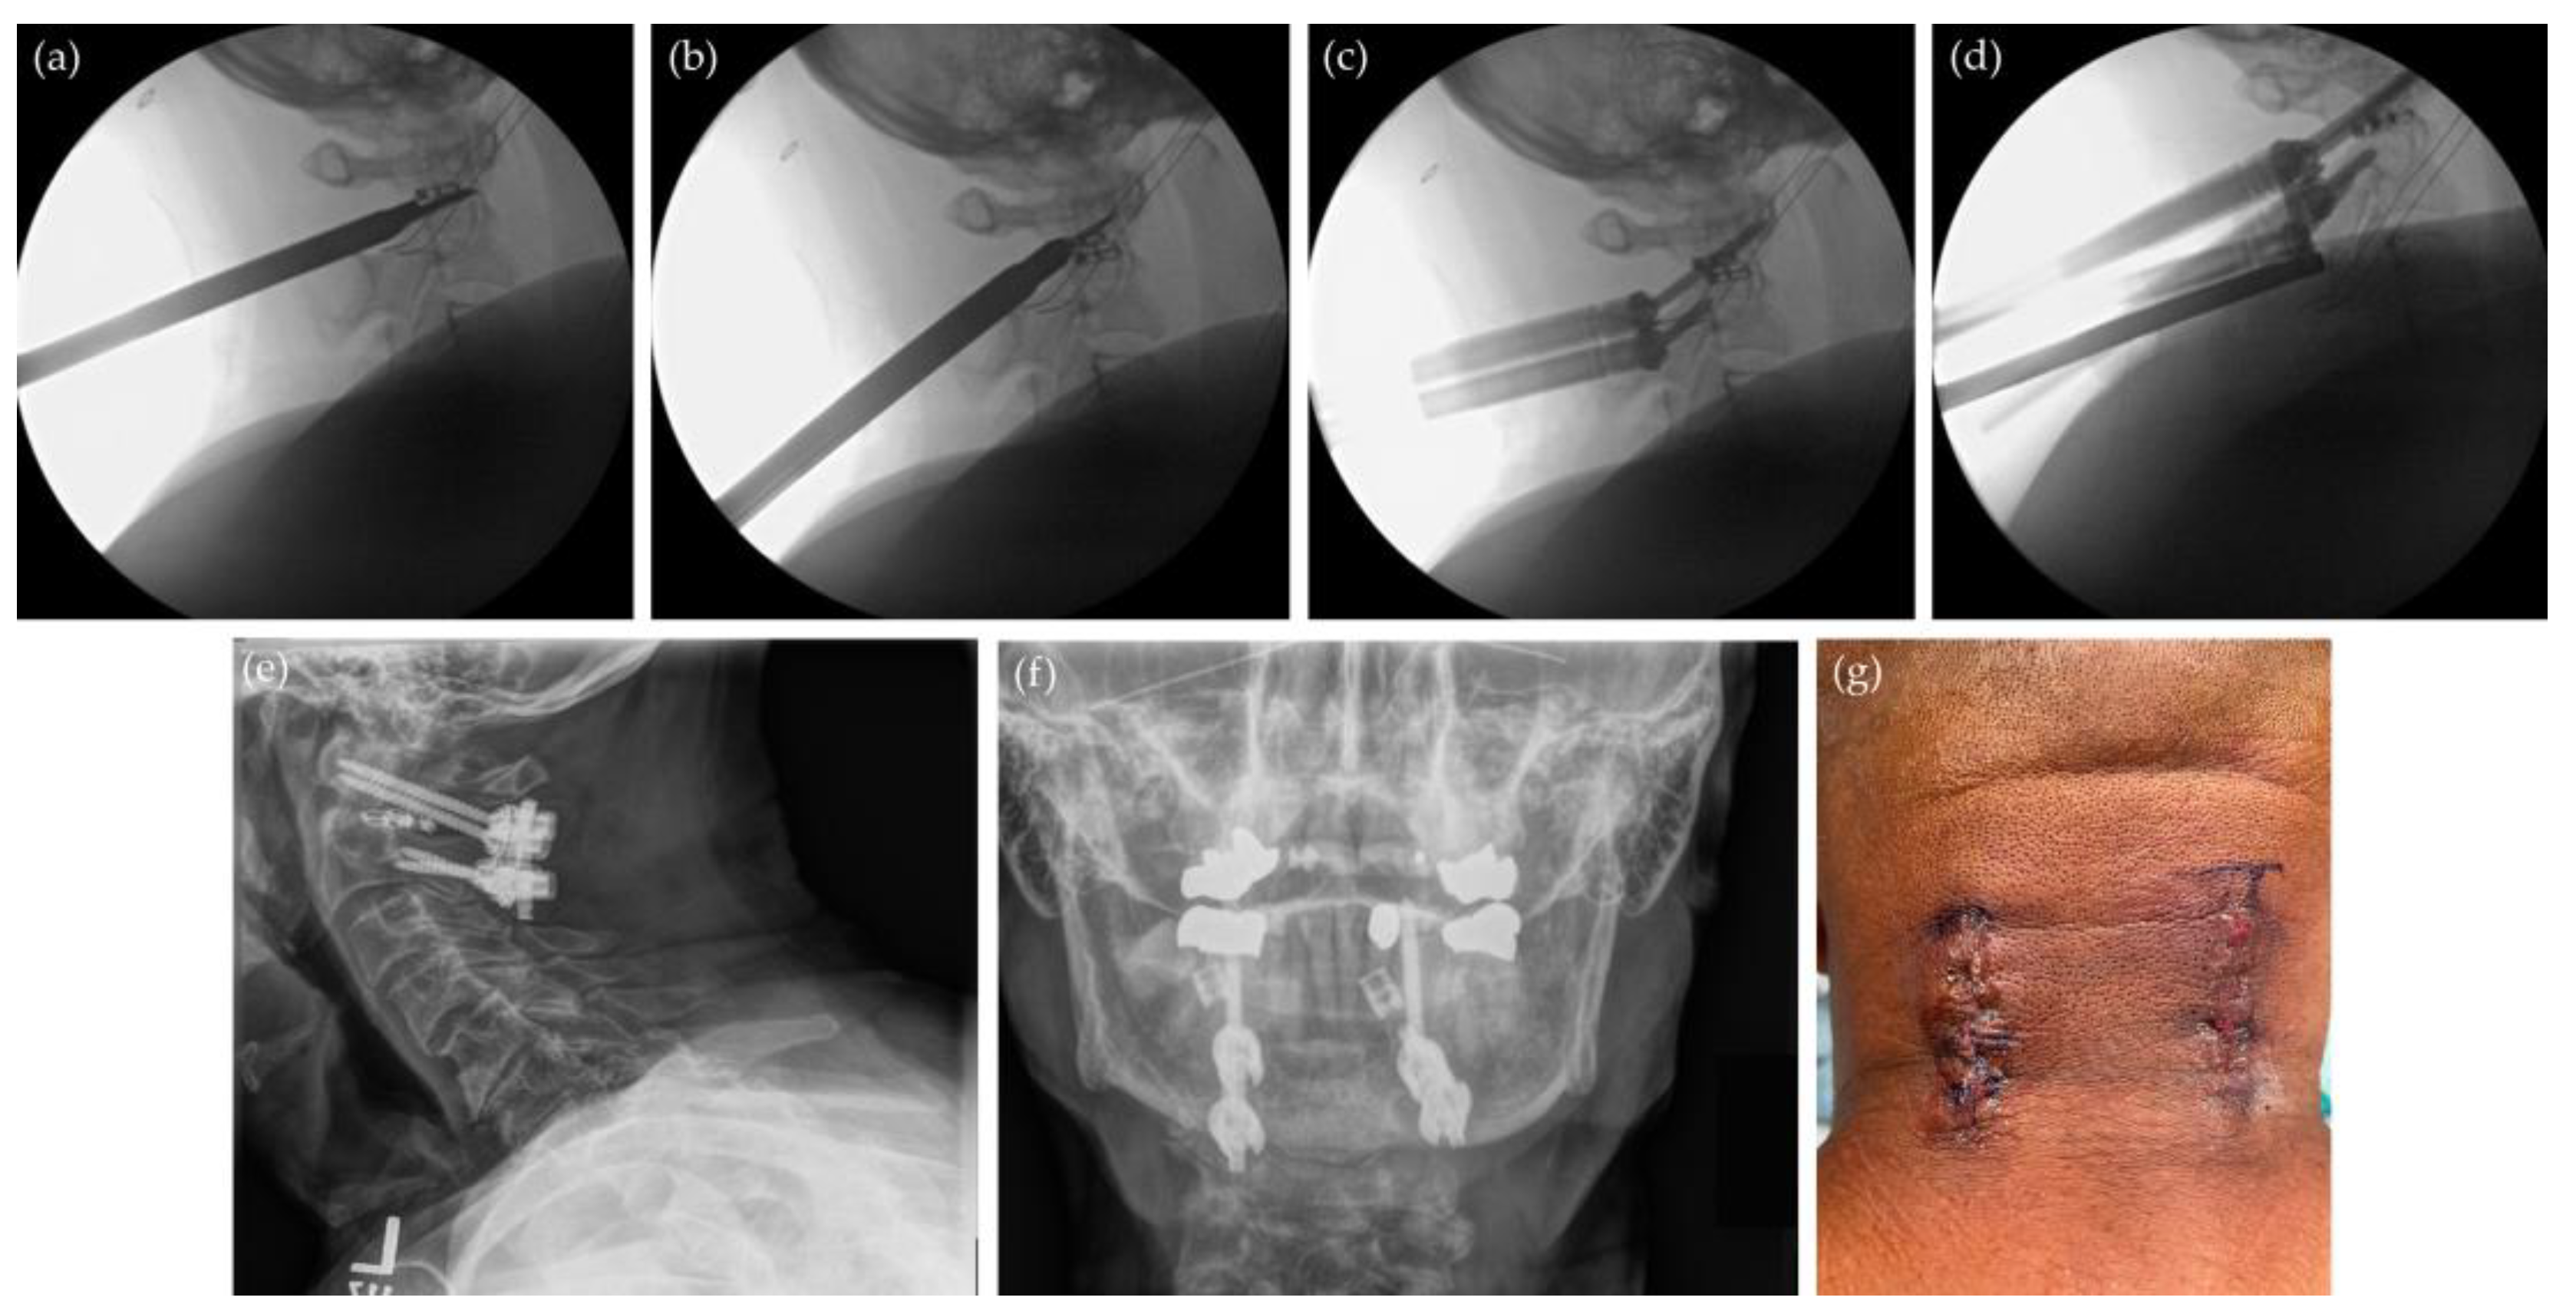

7.1. Minimally Invasive Posterior Cervical Decompression and Fusion